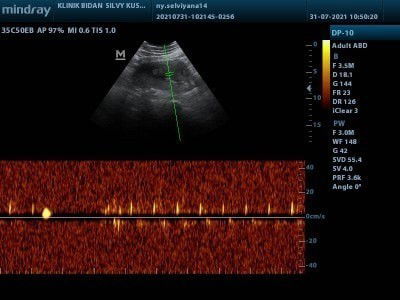

Usg 14 wek di bidan yang berbeda di tempat yang tidak sama sebelum nya, dan apa ini bener

Bun mau tanya Ini usg aku pas 14wek tapi dia kaya bener bener nongol ga percya banget apa iya ini bener kepala dan tangan nya dede bayi aku😥 ##seriusnanya #bantusharing ##ingintahu #pleasehelp #firstbaby